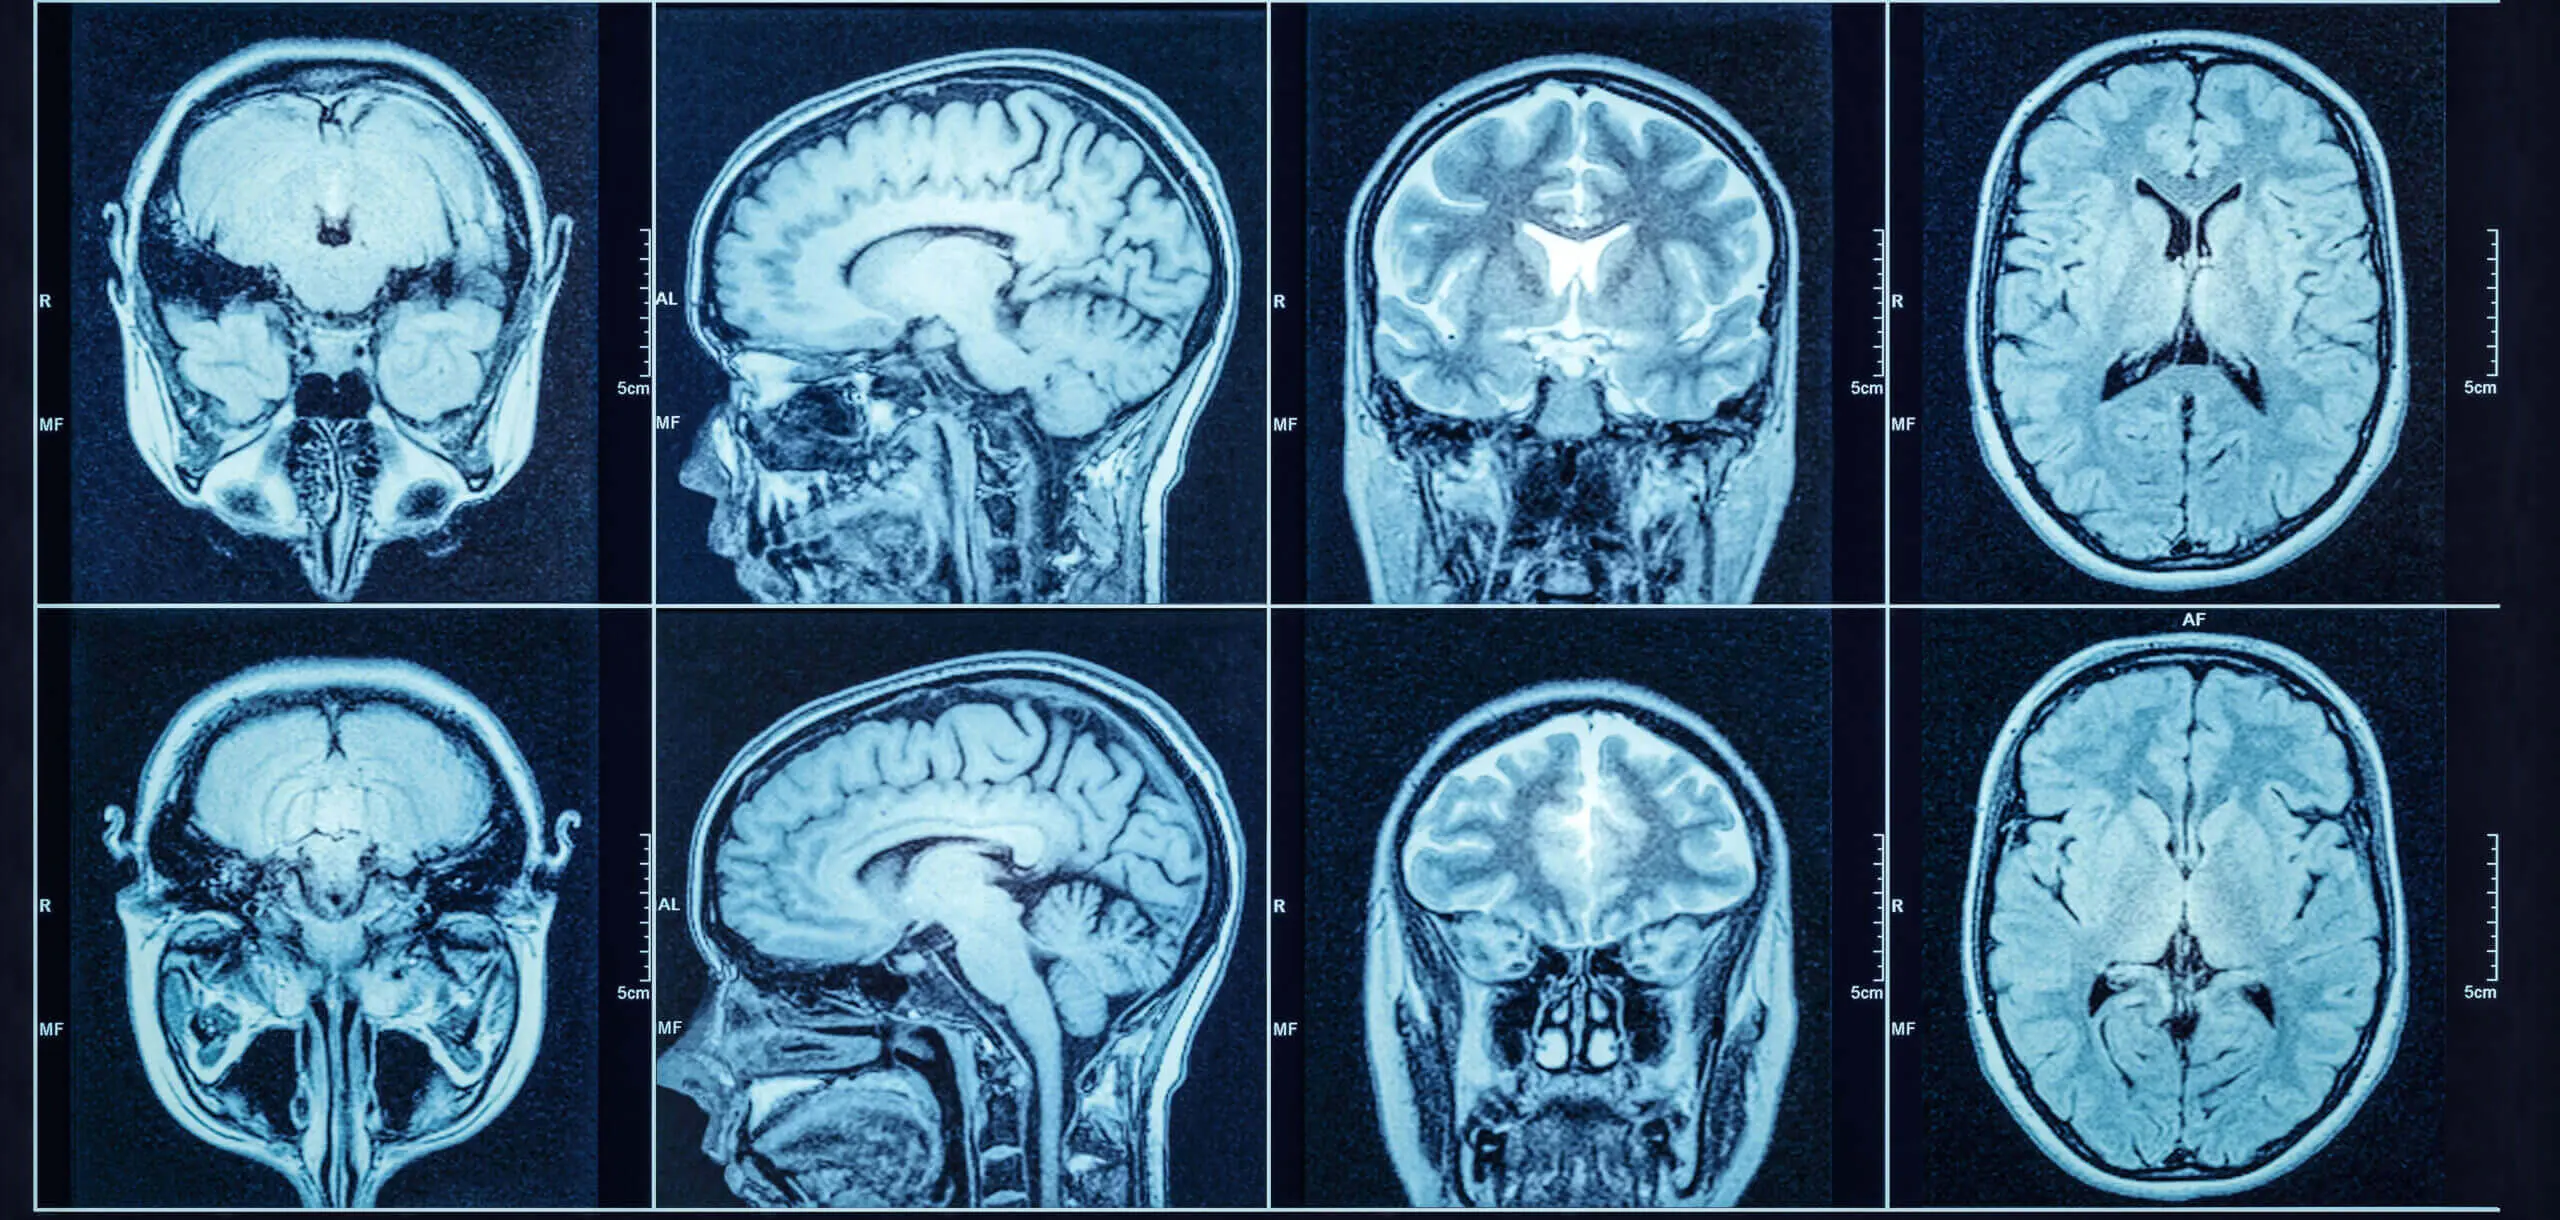

Woman Files Depo-Provera Meningioma Lawsuit After Needing Brain Surgery, Annual MRIsEven after extensive brain surgery, the Depo-Provera brain tumor could return, resulting in a need for yearly MRIs and potential radiation therapy. January 8, 2025 Irvin Jackson Add Your CommentsA Virginia woman has filed a Depo-Provera lawsuit, indicating that she developed an intracranial meningioma after receiving the birth control shots for one year, whichย required her to undergo brain surgery to remove the tumor, and left her with a need for continued medical monitoring.Holli Burket and her husband, Lester, filed the complaint (PDF) in the U.S. District Court for the Eastern District of Pennsylvania on January 3, naming Pfizer, Pharmacia & Upjohn Co. LLC and Pharmacia LLC as defendants. The lawsuit accuses the manufacturers of failing to provide adequate warning to Depo shot recipients about the risks of brain tumors.Depo-Provera is a hormonal birth control shot that was first introduced in 1992, containing a synthetic form of the hormone progesterone, known as medroxyprogesterone. Following decades of advertisements that promoted the quarterly injection as a safe means of preventing pregnancy, Depo-Provera has been widely used by more than 70 million women in the U.S.However, studies published last year raised concerns about the safety of the birth control shot, warning that Depo-Provera causes meningioma brain tumors to develop in some women, which can be life-threatening and often require surgical intervention.This has led to women, like Burket, pursuing an increasing number of Depo-Provera meningioma lawsuits in U.S. District Courts nationwide, each raising similar allegations that women could have avoided brain tumors if the drug makers had provided adequate warnings about the importance of monitoring women receiving the birth control shots.Depo-Provera LawsuitDid you or a loved one receive Depo-Provera injections?Depo-Provera lawsuits are being pursued by women who received birth control shots and developed brain tumors. See if you qualify for a settlement.Learn More about this lawsuitSEE IF YOU QUALIFY FOR COMPENSATIONDepo-Provera LawsuitDid you or a loved one receive Depo-Provera injections?Depo-Provera lawsuits are being pursued by women who received birth control shots and developed brain tumors. See if you qualify for a settlement.Learn More about this lawsuitSEE IF YOU QUALIFY FOR COMPENSATIONAccording to her lawsuit, Burket received Depo-Provera injections from approximately 1994 to 1995. Over time she developed dizziness, slurred speech, fatigue and neck problems.In January 2023, Burket was diagnosed with intracranial meningioma following a magnetic resonance imaging (MRI) test. The scan revealed a 2.5 cm brain tumor, and she underwent brain surgery to have as much of it removed as possible.Despite the successful procedure, doctors warned her that the cancer may return.โPlaintiff may require radiation treatments in the future to prevent recurrence of her meningioma,โ the lawsuit states. โPlaintiff will need to undergo follow-up MRIs annually.โAs a result, Burket presents claims of failure to warn, design defect, negligence, negligent failure to warn, negligent design defect, negligent misrepresentation, fraudulent misrepresentation and breach of warranty. Her husband presents a claim of loss of consortium. They are seeking both compensatory and punitive damages.January 2025 Depo-Provera Meningioma Lawsuit UpdateThe filing comes as a group of plaintiffs are seeking to create a Depo-Provera lawsuit MDL (multidistrict litigation), asking that similar complaints filed throughout the federal court system be consolidated before one judge in the U.S. District Court for the Northern District of California, for coordinated discovery and pretrial proceedings.Both Pfizer and generic manufacturers say they support Depo-Provera lawsuit centralization, but want the MDL based in the Southern District of New York, which is closer to their headquarters.If the JPML agrees to consolidate the lawsuits into a Depo-Provera MDL, all current and future claims filed in federal court will be transferred to one judge for coordinated discovery, pretrial motions and potentially a series of early bellwether test cases.However, if the parties fail to reach Depo-Provera brain tumor settlements or another resolution for the litigation after all pretrial proceedings are concluded, each individual lawsuit may later be remanded back to the U.S. District Court where it was initially filed for an individual trial in the future.The U.S. JPML is scheduled to consider oral arguments on the motion at a hearing scheduled for January 30, 2025, at the Wilkie D. Ferguson, Jr. U.S. Courthouse in Miami, Florida. Written by: Irvin JacksonSenior Legal Journalist & Contributing EditorIrvin Jackson is a senior investigative reporter at AboutLawsuits.com with more than 30 years of experience covering mass tort litigation, environmental policy, and consumer safety. He previously served as Associate Editor at Inside the EPA and contributes original reporting on product liability lawsuits, regulatory failures, and nationwide litigation trends. Tags: Birth Control, Birth Control Shot, Brain Surgery, Brain Tumor, Depo-Provera, Medical Monitoring, Meningioma, MRI, Pfizer Find Out If You Qualify For a Depo Provera LawsuitMore Depo-Provera Lawsuit Stories Depo-Provera Meningioma Warning Update Should Be Added to Birth Control Shot: Lawsuit April 22, 2026 Hearings on Evidence That Depo-Provera Causes Meningioma Brain Tumors Set for Late June 2026 April 15, 2026 High-Risk Brain Tumor From Depo-Provera Requires Frequent Monitoring, Lawsuit Claims April 6, 2026 0 Comments PhoneThis field is for validation purposes and should be left unchanged.Share Your CommentsFirst Name*Last NameEmail* Shared Comments*This field is hidden when viewing the formI authorize the above comments be posted on this page Yes NoPost Comment I authorize the above comments be posted on this pageWeekly Digest Opt-In Yes, send me a weekly email with the latest lawsuits, recalls and warnings.Want your comments reviewed by a lawyer?To have an attorney review your comments and contact you about a potential case, provide your contact information below. This will not be published.Contact Phone #Alt Phone #Private CommentsNOTE: Providing information for review by an attorney does not form an attorney-client relationship.CAPTCHAGA SourceGA CampaignGA MediumGA ContentGA TermΔ MORE TOP STORIES Judge Says Suboxone โSchedule Aโ Lawsuits Should Be Filed Individually or Dismissed (Posted: today)Two years after allowing thousands of incomplete Suboxone tooth decay lawsuits to be submitted due to statutes of limitation laws, a federal judge says those cases should be filed individually or dismissed.MORE ABOUT: SUBOXONE TOOTH DECAY LAWSUITCourt Outlines Plan To Prepare Suboxone Tooth Decay Lawsuits for Trial in Early 2028 (04/02/2026)Suboxone Film Lawsuit Filed by 46 Users Alleging Drug Makers Ignored Years of Dental Injury Reports (03/03/2026)100 Suboxone Film Tooth Decay Lawsuits Selected for Next Phase of Bellwether Discovery (02/13/2026) JPML Sets Hearing Over Spinal Cord Stimulator Lawsuit Consolidation for May 28 (Posted: 3 days ago)In late May, a panel of federal judges will hold oral arguments over whether all federal spinal cord stimulator lawsuits should be consolidated before one judge for pretrial proceedings.MORE ABOUT: SPINAL CORD STIMULATOR LAWSUITSCS Injury Lawsuit Alleges Unlicensed Abbott Representatives Modified Device After Implantation (04/20/2026)WaveWriter Alpha Lawsuit Claims Defective Spinal Cord Stimulator Caused Pain and Surgical Removal (04/14/2026)Boston Scientific Neuromodulation Lawsuit Claims Spinal Cord Stimulator Exacerbated Chronic Pain (04/08/2026) Fire Pit Burn Lawsuits Mount as CPSC Issues Warning Over New Flame Jetting Injuries, Death (Posted: 4 days ago)As the number of lawsuits over tabletop fire pits continues to grow, the CPSC has issued a warning indicating that despite a consumerโs death linked to one product, the manufacturer has not agreed to remove the devices from the market.MORE ABOUT: TABLETOP FIRE PIT LAWSUITKizzby Tabletop Fire Pit Lawsuit Claims Alcohol-Fueled Bowl Exploded, Igniting Womanโs Hand (04/01/2026)Flame Jetting Lawsuit Claims Amazon Tabletop Fire Pit Erupted, Caused Severe Burns (03/19/2026)Brookstone Fire Pit Lawsuit Filed After Woman Suffers Second, Third Degree Burns (01/19/2026)